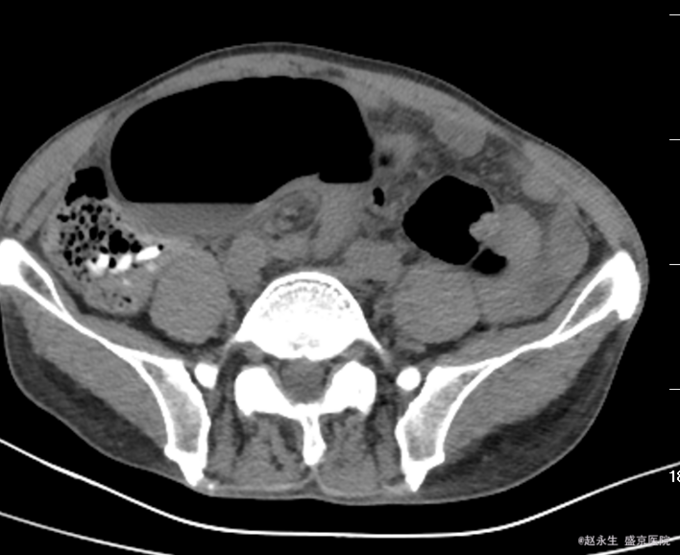

查体::腹膨隆,未见肠型及蠕动波,未触及明确包块,全腹压痛,反跳痛及肌紧张,肝区叩痛阴性,肾区叩痛阴性,Murphy征阴性。肝浊音界未见减少,移动性浊音阳性,未闻及肠鸣音。 辅助检查:急诊查腹部CT平扫提示:乙状结肠扭转,肠梗阻.盆腔多发渗出,积液.

诊断:乙状结肠扭转 治疗:急诊全麻下行剖腹探查,乙状结肠部分切除,远端闭锁,近端造瘘术。术中探查见左侧腹腔巨大肠畔,张力较高,肠壁因扩张导致菲薄,肠壁暗红有点状缺血坏死征象,有一处肠壁浆膜裂开,有少许出血,扩张肠管周围及盆腹腔有草黄色渗出,吸净渗出,轻轻将扩张肠管娩出腹壁外,证实扩张的肠管为乙状结肠,仔细检查,见乙状结肠系膜较长,肠管顺时针扭转360°形成完全性肠梗阻,横结肠,降结肠扩张,有较多内容物,未触及肿瘤,胃空虚。